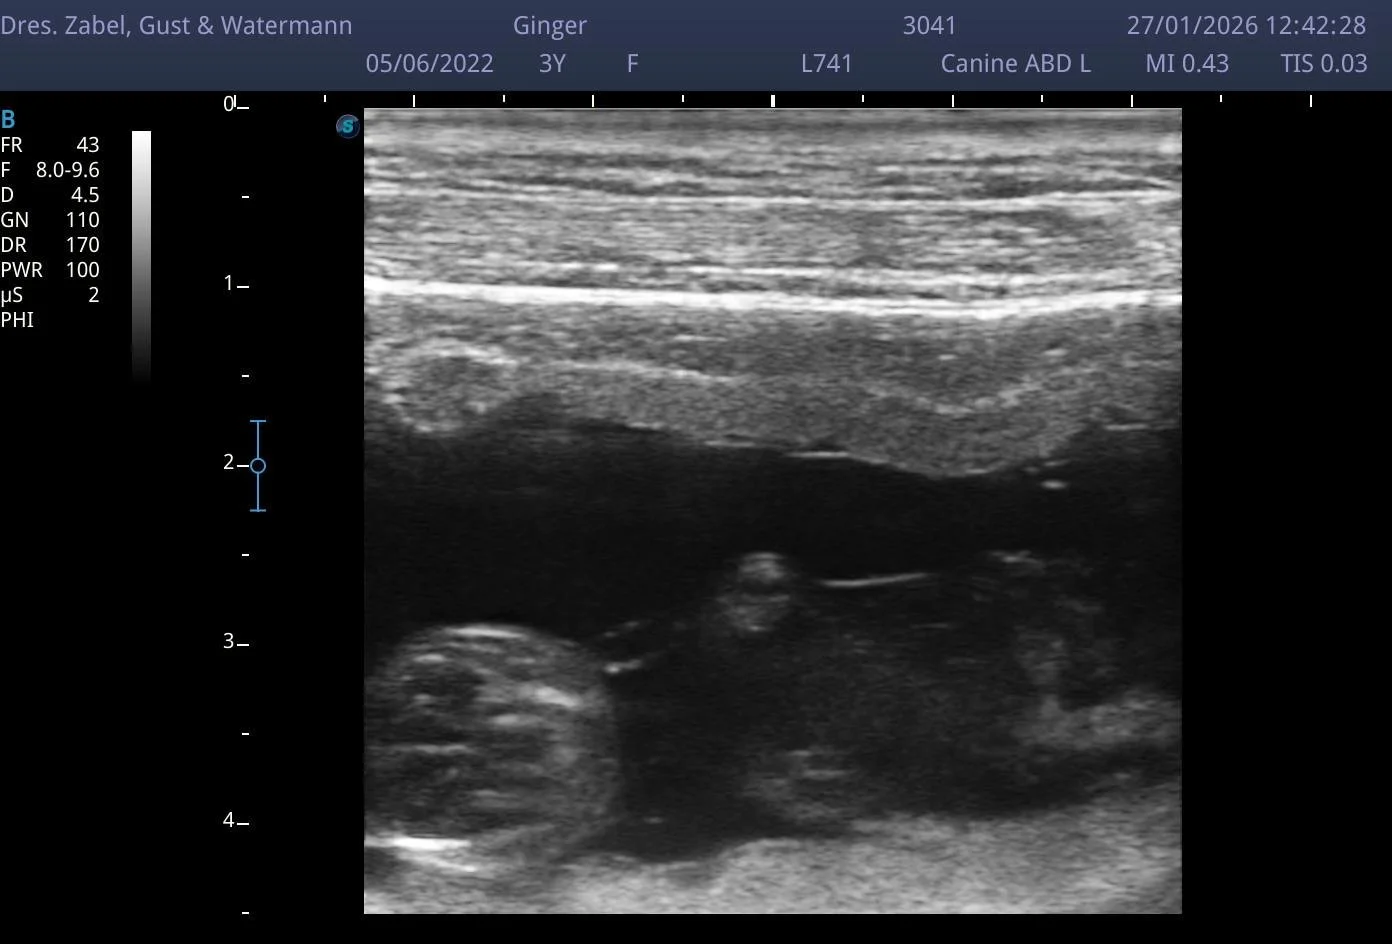

Beim Ultraschall konnten bereits zwei Welpen gesehen werden – es dürfen also mindestens zwei kleine Labradore erwartet werden.